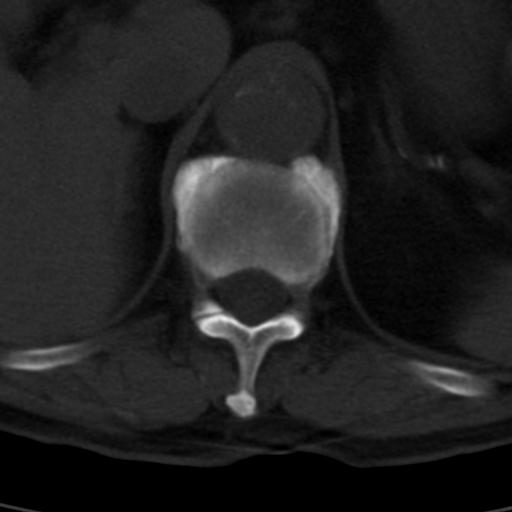

男性 82 主动脉夹层 请大家看看椎体是什么改变啊

腰椎退行性变,明显的骨赘形成,所指低密度灶为正常松质骨。